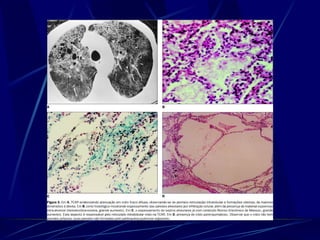

Coccidioides immitis Dimórfico (hifa con artroconidia en ambiente y esférulas con endosporas en tejidos) En el desierto (Suroeste de USA)

Coccidioides immitis Enfermedad Valley Fever:  neumonia que resuelve, eritema nodoso, artritis Lesiones pulmonares calcifican Sistémica en SIDA:  meningitis, lesiones mucocutáneas. Se diseminan en el 3er trimestre del embarazo!

Coccidioides immitis Dimórfico(hifa con artroconidia en ambiente y esférulas con endosporas en tejidos) En el desierto (Suroeste de USA)

Coccidioides immitis EnfermedadValley Fever: neumonia que resuelve, eritema nodoso, artritis Lesiones pulmonares calcifican Sistémica en SIDA: meningitis, lesiones mucocutáneas. Se diseminan en el 3er trimestre del embarazo!